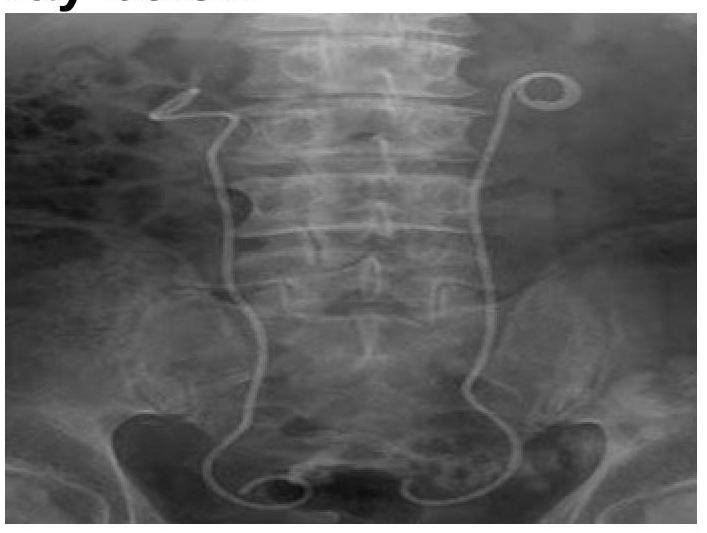

Question 5: What is the structure seen in the X-ray?

- A. Stent (Correct Answer)

- B. Surgical clips

- C. Foley catheter

- D. Intravesical wire

Explanation: ***Stent*** - The image clearly shows **bilateral coiled structures** (pigtails) at the proximal and distal ends within the renal pelvis and bladder, which are characteristic features of **double J stents (ureteral stents)**. - These devices are used to maintain patency in the **ureters**, often to bypass obstructions or facilitate urine drainage. *Surgical clips* - **Surgical clips** are typically small, dense, metallic objects used to ligate vessels or tissue, appearing as tiny, bright specks on X-rays. - The structures seen in the image are long, tubular, and coiled, which is inconsistent with the appearance of surgical clips. *Foley catheter* - A **Foley catheter** is a flexible tube inserted into the bladder to drain urine, sometimes with a balloon tip. - It would typically be seen entirely within the **bladder**, and its path would not extend bilaterally into the renal pelvis as shown. *Intravesical wire* - An **intravesical wire** (a wire entirely within the bladder) would appear as a coiled or linear structure confined to the bladder itself. - The structures in the image extend from the renal region down into the bladder, traversing the **ureters**, which is not typical for an intravesical wire.